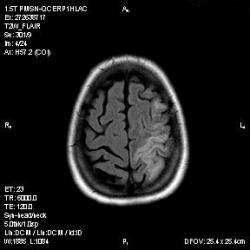

Из анамнеза - Женщина 45 лет. За год похудела на 15 кг (со слов матери), в последние месяцы случались эпизоды потери сознания. Онкозаболеваний и прочая в анамнезе нет. Сознание спутанное, из особенностей в анализах только подъем амилазы крови.

К сожалению, не владею методом КТ, но учитывая наличие неравномерного уплотнения в мозговых структурах с элементами очаговых "вкраплений", единственное, что приходит на ум - это рассеяный склероз. Хотелось бы уточнить, что беспокоило пациентку в течение последнего года кроме потери веса и эпизодов потери сознания? Была ли какая-либо очаговая неврологическая симптоматика? Отмечались ли какие-либо расстройства в двигательной или чувствительной сфере и т.д.? С уважением Helenmar.

И это точно не РС, т.к. характер очагов другой, ни один из них не копит контраст, нет субтенториальных очагов (извиняюсь, я этого в сообщении не указал), нет клиники.

"Раскрою" карты. Мы подумали о синдроме MELAS (mitochondrial encephalomyopathy, lactic acidosis and stroke) - дословно, митохондриальная энцефаломиелопатия, лактоацидоз и инсульт. В качестве дифференциальной диагностики можно было бы предположить вирусный энцефалит, но опять-таки, расположение очагов смущает - только с одной стороны и в абсолютно различных структурах.

В данном случае мы видим импульную последовательность FLAIR - режим с подавлением сигнала от воды, поэтому ликвор гипоинтенсивен, а также (вторая серия) - изображения, взвешенные по T1 после введения контрастного препарата. На T1 жидкость (ликвор) также представляется гипоинтенсивной. Зато на этих сериях гиперинтенсивны сосуды, т.к. контрастное вещество циркулирует в кровяном русле.

Изменения носят сосудистый характер. Процесс достаточно острый, имеется объемное воздействие, борозды левой гемисферы компремированы. По поводу MELAS синдрома очень сомневаюсь, почему поражена только левая гемисфера? Надо делать МР-ангиографию, смотреть нет ли стеноза

MELAS синдром - дебютирует с детских лет, характерен целый комплекс неврологических проявлений, заболевание генетическое, поражение системное, хотя есть множество вариантов митохондриального поражения, все же сомнительно. Хотелось бы акцентировать внимание, что гиперинтенсивные очаги есть в мозолистом теле, поражены выражено перивентрикулярные отделы, U -пути, белое вещество, поэтому так категорично демиелинизацию не вычеркивала бы из дифряда ( хотя тоже нетипично односторонее поражение). Думаю, для объективных выводов все же мало общей информации о пациентке, были ли клинические эпизоды раньше, чем объяснить такую потерю веса (возможно есть проявление паранеопластического синдрома?). Ну и МРТ-контроль в динамике, ангиография.

Да, неоднозначный случай. Точно не РС и не ОНМК. Я бы написала асимметричную лейкоэнцефалопатию неясного генеза. Можно было бы думать о лимфоме (полифокальное поражение, да еще мозолистое тело вроде бы задействовано (эх, сагиттальчики бы)). Но! Учитывая отсутствие накопления КВ.... Ну и надо исключать интоксикацию, всяческие аутоиммунные процессы (в т.ч. и васкулиты), сахарный диабет, ну и естественно наследственную патологию обменных процессов. УУУх! Вот.......

Имхо ишемический онмк в бассейне сма. Особенно показательны 5-й и 6-й файлы, отграничение как раз на границе бассейнов средней и перикаллёзной. Плюс одностороннее поражение.